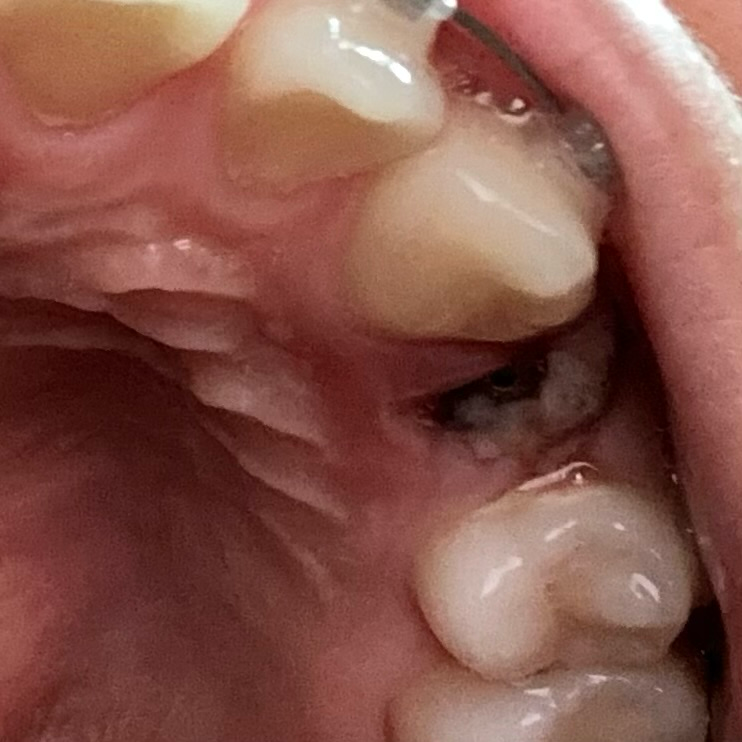

발치 후 5일차인데 상태 어떤가요?

잘 회복되고 있는건가요? 위쪽에 흰부분은 뭔가요??

• 1번 째 사진

사진으로 보아서는 정상적인 회복과정으로 보여지며 혈병 및 섬유화가 적절히 이뤄지고 있습니다. 일주일 정도는 빨대 사용을 금하는 것이 좋으며 그때까지 부드럽고 자극적이지 않은 음식 섭취를 하는 것이 도움이 될 수 있습니다.

5일정도 되셧다면 일반식사를 하셔도 될것같습니다. 하얗게 보이는 부분은 잇몸이 치유되면서 자연스럽게 생기는 현상이니 너무 걱정하지 않으셔도 될것같습니다.

2) 발치 후 치유과정에는 문제가 없이 진행되고 있는 것 같습니다. 하얀 건 치유과정에서 나오는 육아조직 산물입니다.